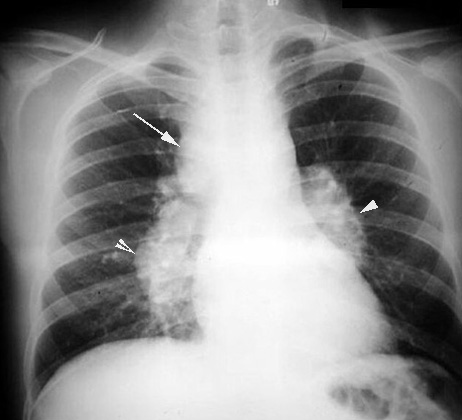

Sarcoidosis

Arrowheads: Bilateral symmetrical hilar adenopathy

Arrow: Paratracheal nodes enlarged.